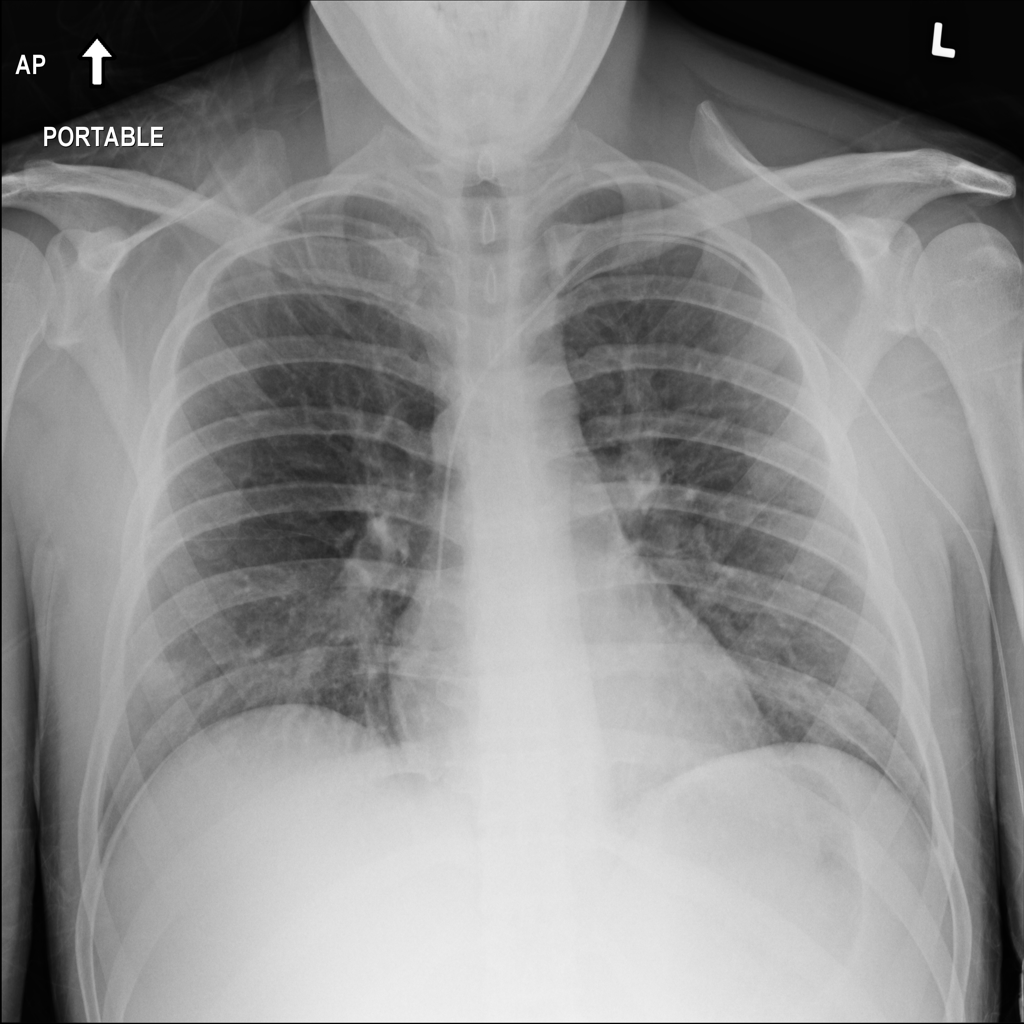

Nodule

A nodule is a small rounded opacity in the lung or chest field. It is a descriptive imaging finding that can be benign or more concerning depending on size, appearance, and context.

Showing up to 90 reference images for Nodule.

PAT-50E5 · IMG-000Nodule

PAT-50E5 · IMG-000

PA